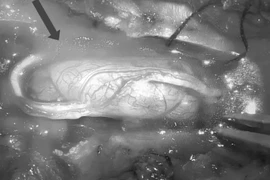

Mới đây, khoa Ngoại Thần kinh, Bệnh viện Trung ương Quân đội 108 vừa phát hiện và phẫu thuật thành công cho bệnh nhân nữ trẻ tuổi có khối u tủy trong ống sống ngực.